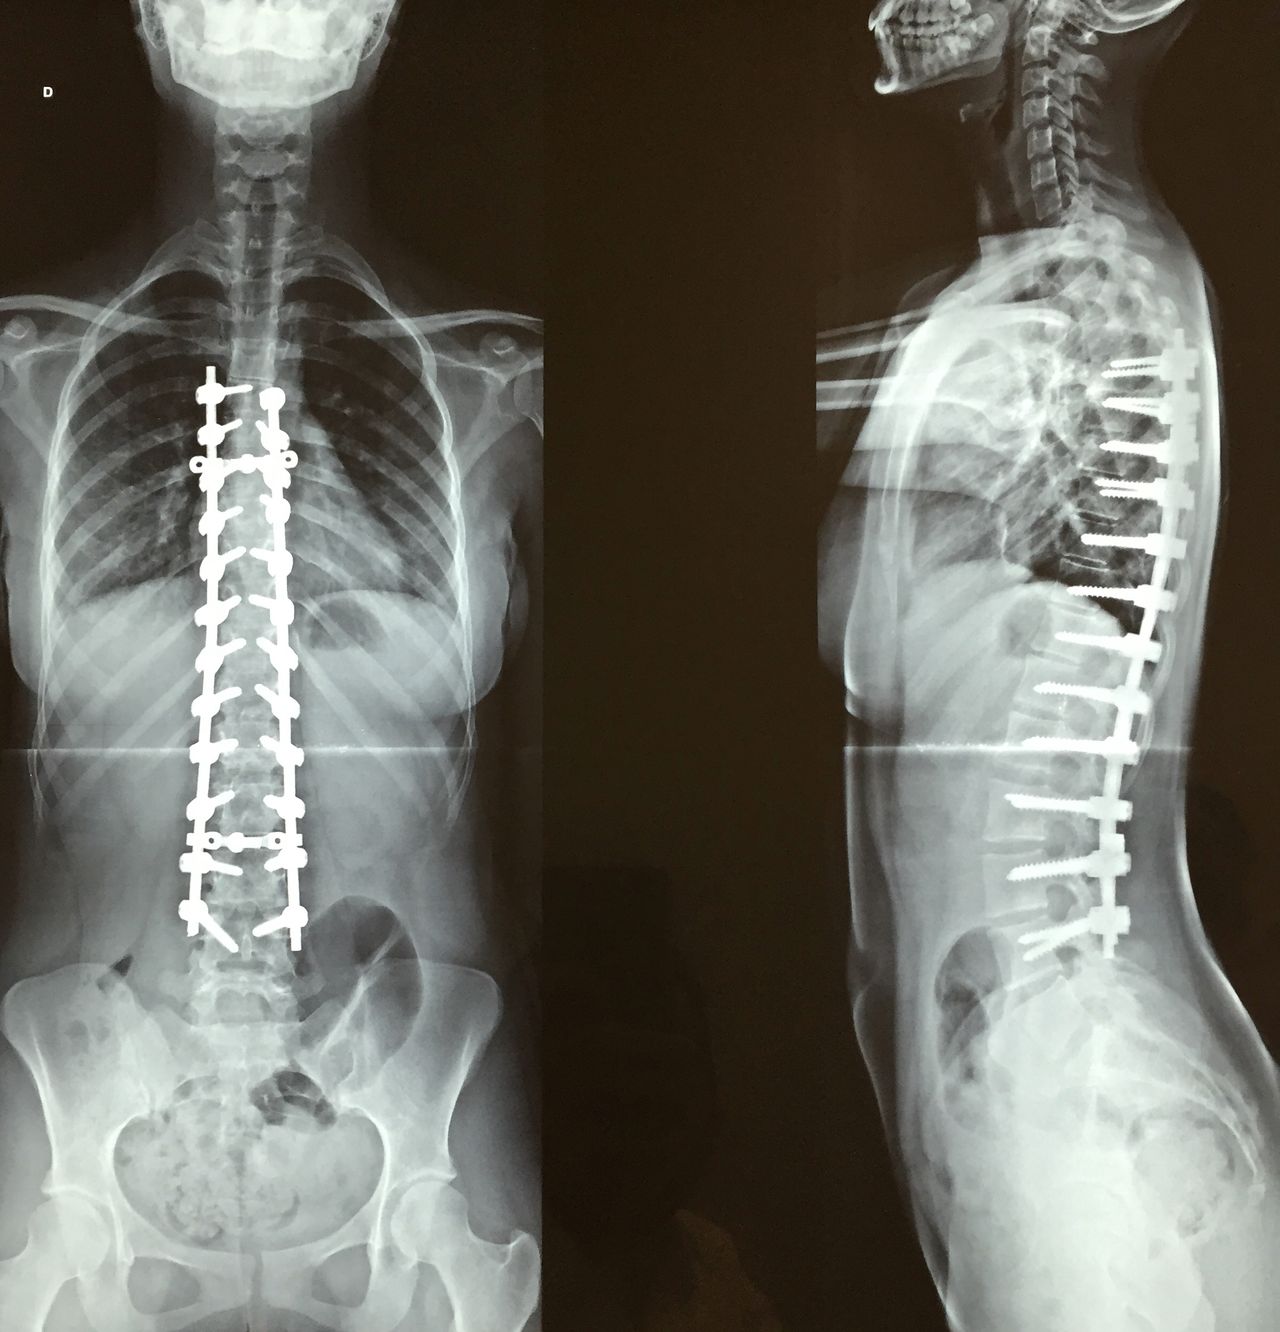

Escoliose

Deformidade da coluna que pode ocorrer por tendências genéticas, síndromes, doenças neurológicas ou desgaste intenso da coluna. Quando diagnosticada precocemente, deve ser acompanhada pois em alguns casos o uso de colete pode ser prescrito. Em casos onde há progressão da deformidade, compressão de nervos, dor intratável, pode-se instituir cirurgias corretivas para a deformidade.